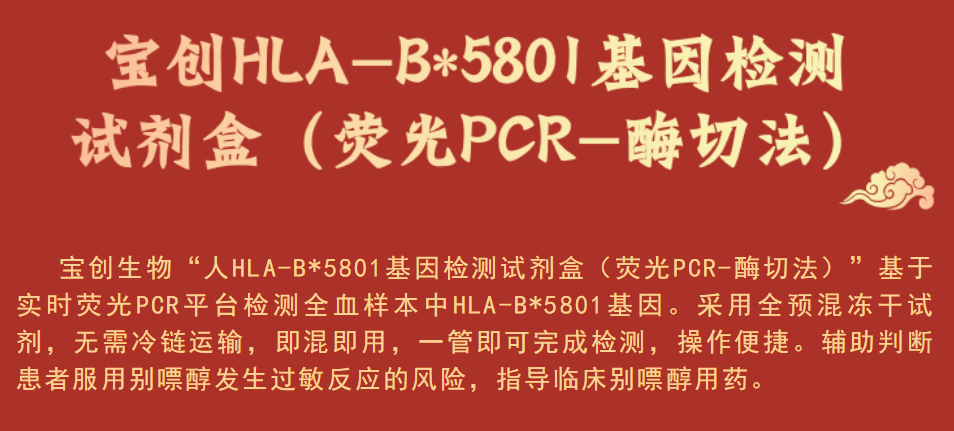

在高尿酸血症及痛风患者降尿酸治疗的药物当中,别嘌醇因其疗效显著、副作用较小、加之价格实惠,一直以来都是广泛推荐的一线治疗药物。但此药物的副作用也不容小觑!

部分患者在服用别嘌醇后发生了严重皮肤不良反应(SCARs),包括Stevens-Johnson综合症,中毒性表皮坏死松懈症,高敏反应综合征,病死率分别为 5%、10% 及 30%。不仅对患者造成严重的身体损伤甚至危及生命,还会增加患者的经济负担[2]。

HLA-B*5801:人类白细胞抗原B位点5801基因的简称。人类白细胞抗原(HLA)是细胞表面的抗原呈递蛋白,负责免疫系统调节,参与药物超敏反应的发病机制。

研究发现 :

HLA-B*5801 基因与亚裔人群服用别嘌醇引起的严重皮肤不良反应显著相关。服用别嘌醇后出现严重不良反应的患者中HLA-B*5801 基因携带率为 100%[3],且中国人群HLA-B*5801 基因频率比其他地区人群频率更高,可达 8%-20%[4]。研究显示,在服用别嘌醇前进行 HLA-B*5801 基因检测可显著降低别嘌醇引起的严重皮肤不良反应的发生率。